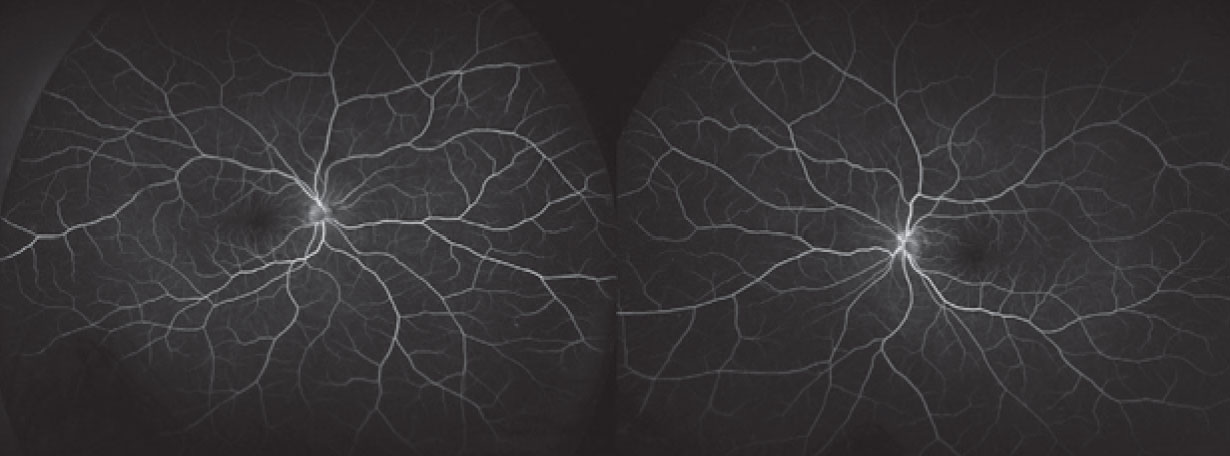

Fluorescein angiography demonstrated a normal vascular pattern in both eyes. There was no evidence of dye leakage from the microvasculature or leakage into the collections of subretinal fluid (Figure 4).

| Figure 4. Fluorescein angiography doesn’t show any abnormal dye leakage or pooling |

The understanding of MEKAR has evolved from case reports and case series.10-12 SRF has been noted on examination in up to 90 percent of patients undergoing treatment with a MEK inhibitor. When it occurs, it’s bilateral in more than 90 percent of cases.13,14 Intensive monitoring of some clinical trial patients have shown rapid accumulation of SRF (within three hours of administration of the MEK inhibitor) followed by even more rapid resolution (by the fourth hour), although a large portion of patients continue to have SRF at their final follow-up visit.13 As this patient demonstrated, in spite of the SRF, fluorescein angiography doesn’t demonstrate pooling or leakage in

MEKAR.